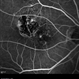

- fluorescein angiogram (FA), FA early phase, MERGE, microaneurysms

- Early FA, right eye, with choroidal melanoma-stable, and a few tiny microaneurysms showing leakage in re-circulation phase.